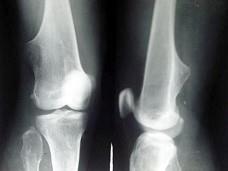

女,15岁,发现大腿远端肿块1周,无明显疼痛,结合图像,最可能诊断是?(?)A.骨质增生B.软骨瘤C.骨肉瘤D.骨瘤E.骨软骨瘤

问题 女,15岁,发现大腿远端肿块1周,无明显疼痛,结合图像,最可能诊断是?(?)

选项 A.骨质增生 B.软骨瘤 C.骨肉瘤 D.骨瘤 E.骨软骨瘤

答案 E